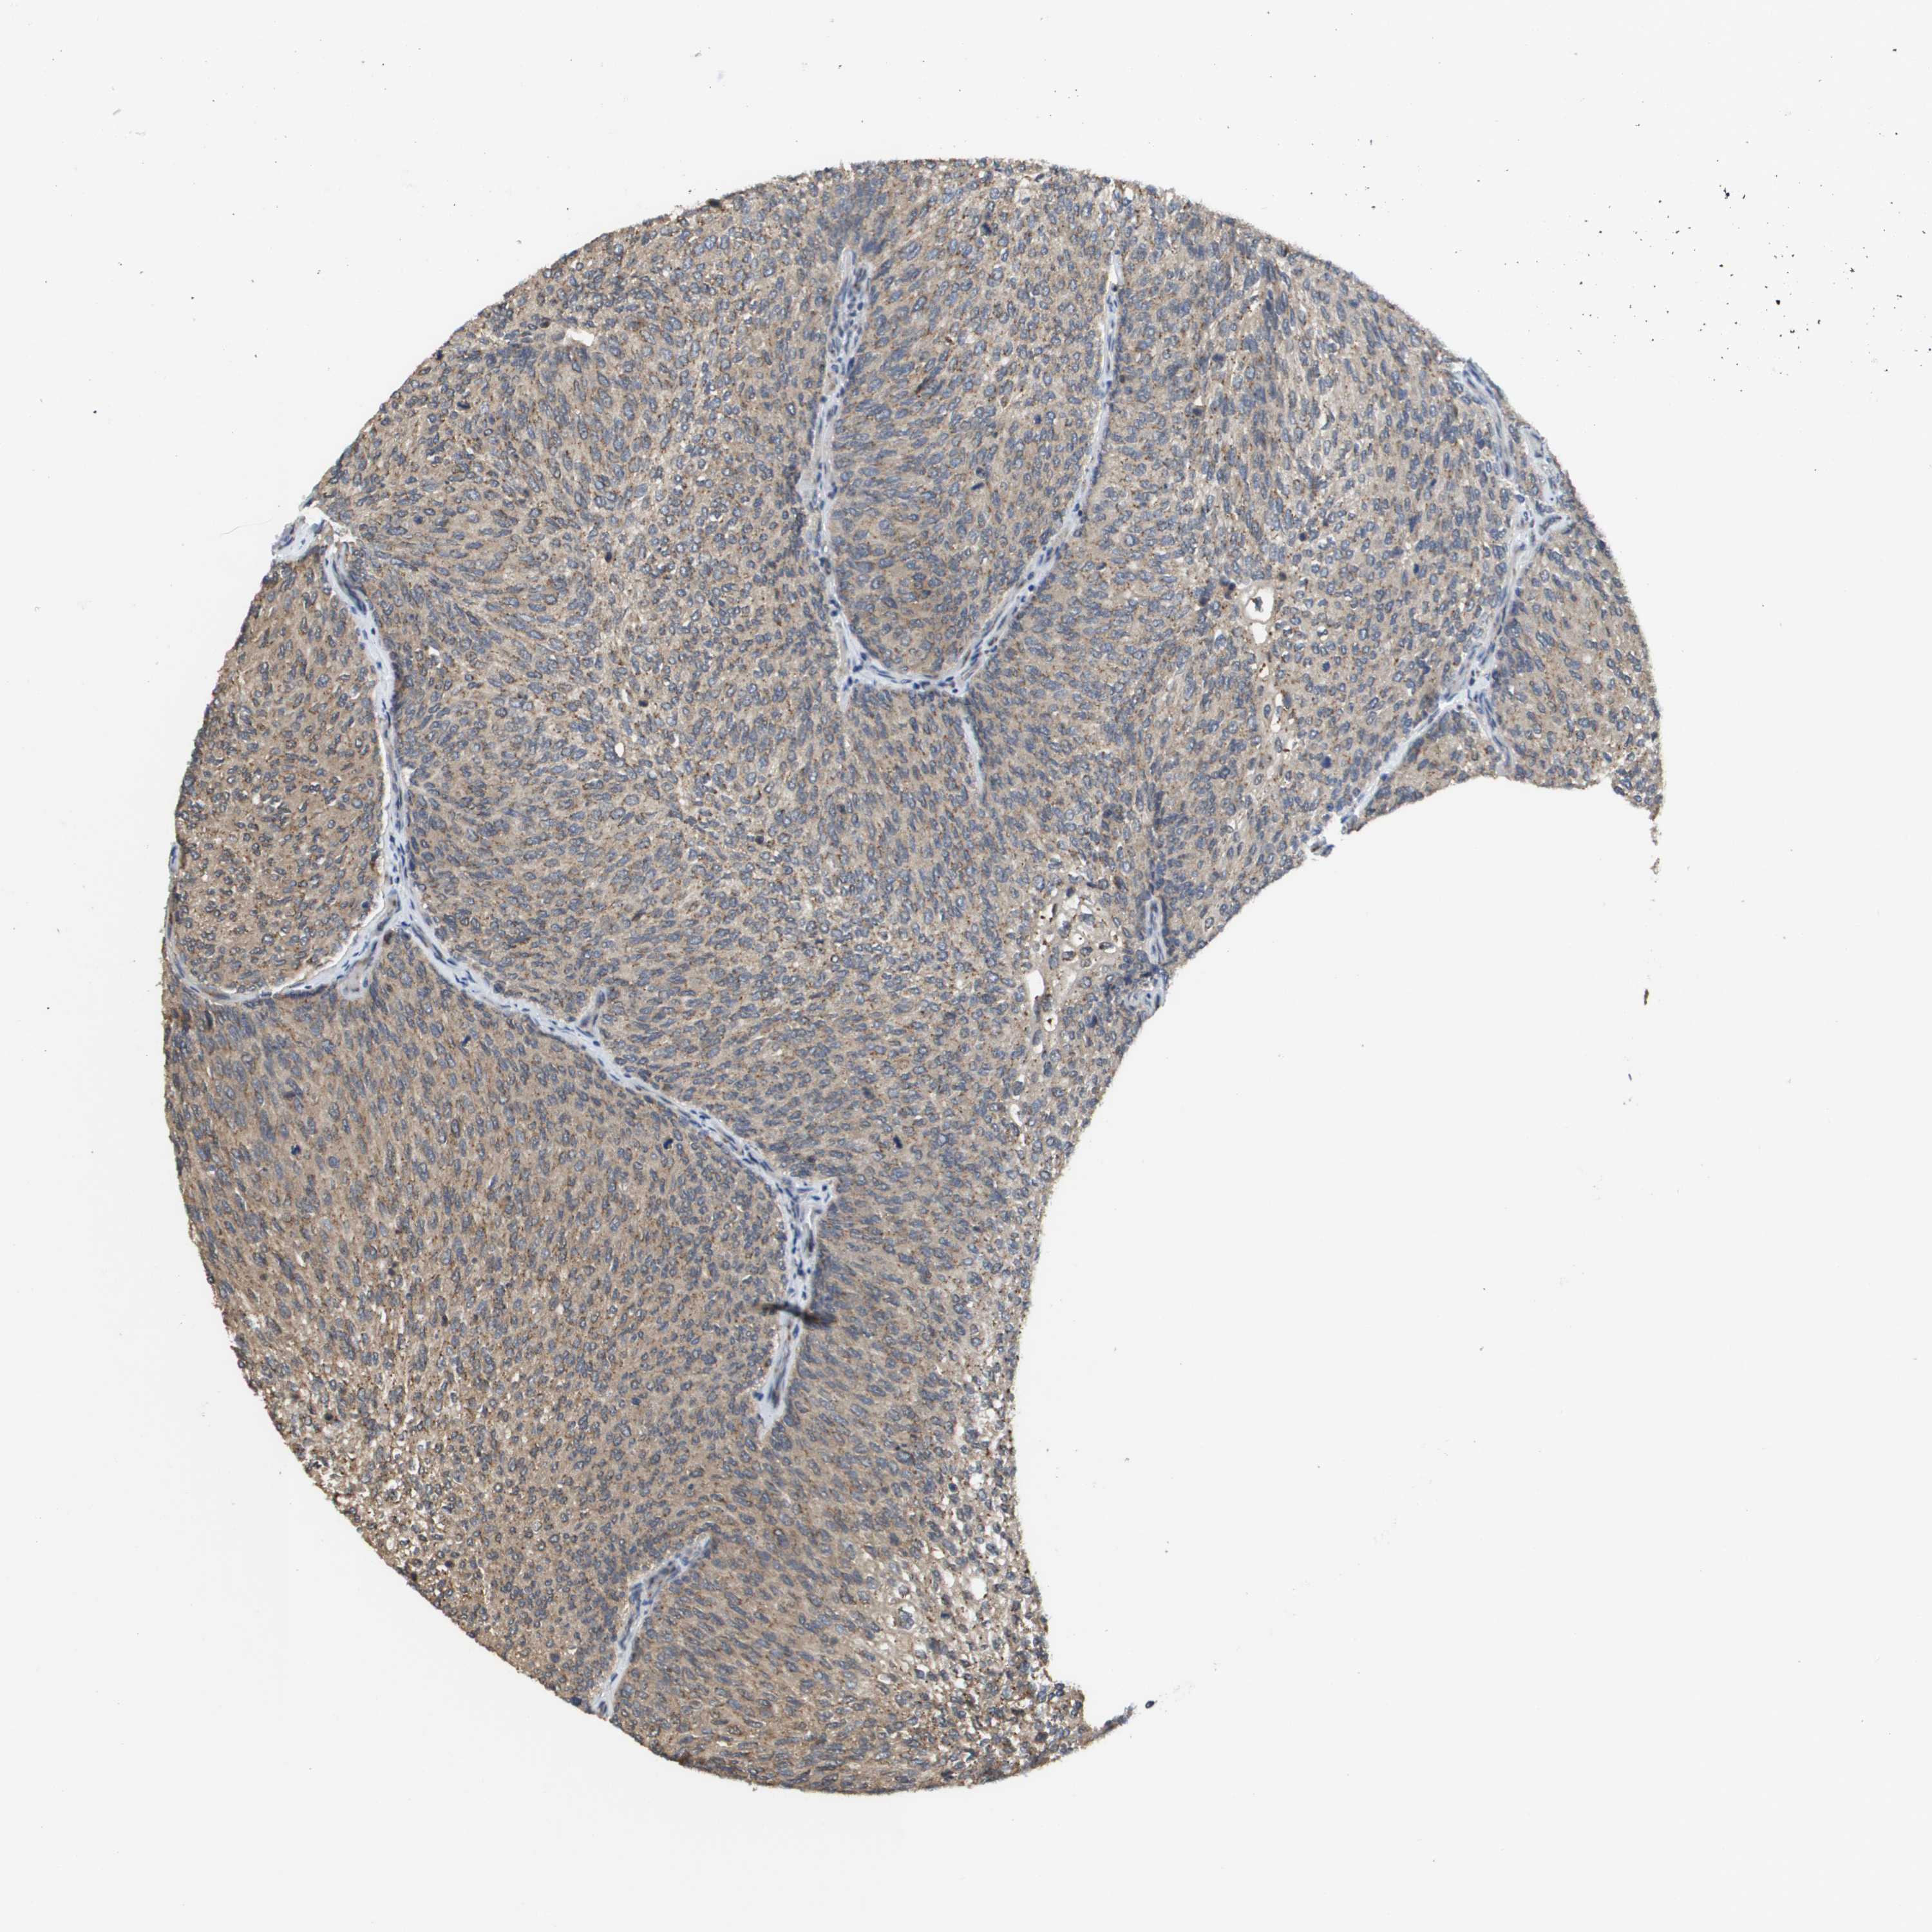

UROTHELIAL CANCER - Protein expressioni

A mouse-over function shows sample information and annotation data. Click on an image to view it in a full screen mode. Samples can be filtered based on level of antibody staining by selecting one or several of the following categories: high, medium, low and not detected. The assay and annotation is described here.

Note that samples used for immunohistochemistry by the Human Protein Atlas do not correspond to samples in the TCGA dataset.

Antibody stainingi

Antibody staining in the annotated cell types in the current human tissue is reported as not detected, low, medium, or high, based on conventional immunohistochemistry profiling in selected tissues. This score is based on the combination of the staining intensity and fraction of stained cells.

Each image is clickable and will lead to virtual microscopy that enables deeper exploration of all samples and also displays staining intensity scores, fraction scores and subcellular localization as well as patient and tissue information for each sample.

Antibody HPA006277

Antibody HPA006507

Antibody CAB017027

Staining

High

Medium

Low

Not detected

Intensity

Strong

Moderate

Weak

Negative

Quantity

>75%

75%-25%

<25%

None

Location

Nuclear

Cytoplasmic/membranous

Cytoplasmic/membranous,nuclear

Urothelial carcinoma, Low grade

Urothelial carcinoma, High grade